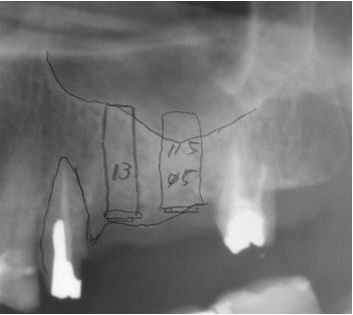

2.サイナスリフト症例(症例 8 )

骨が6mm未満では前述のソケットリフトは長期予後の観点から適応しにくく、骨を確実に増やすにはサイナスリフトの方が適しています。

サイナスリフトとは、上顎洞の側面骨に穴を開け、日ジョイに薄い上顎洞粘膜を剥離し、できた空間に骨補填材を入れ、造骨する手術です。

当院では、サイナスリフトは静脈内鎮静法を併用し局所麻酔で通院で可能です。また、手術時間は片側で約20分で、両側に必要な場合は同時に行い、約40分です。たいていの場合は、インプラントの埋め込みも行いますので、インプラント1本につき約10分ですので、片側サイナスリフトとインプラント2本埋め込みでは約40分で手術は終わります。